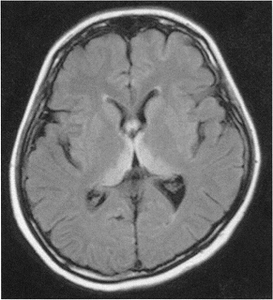

インフルエンザウイルスの感染が原因で脳に障害が生じた病気です。

診断のために、インフルエンザの迅速キットなどのウイルス検査や、頭部MRI検査、髄液検査、脳波検査などを行います。